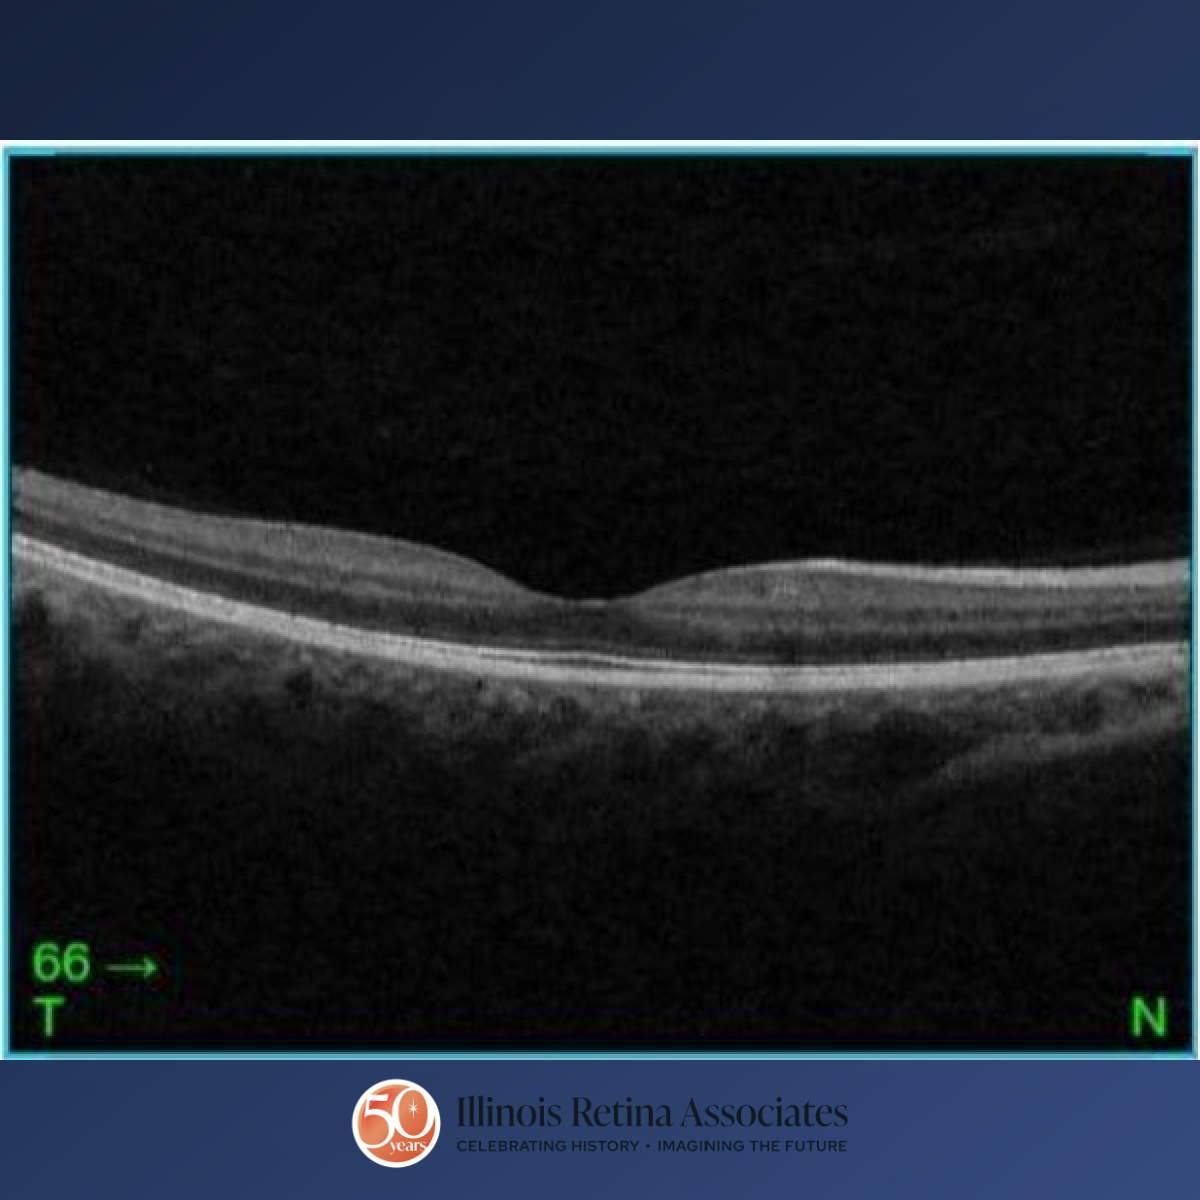

Visual acuity was 20/25 in the right eye (OD) and 20/40 OS. Intraocular pressures were within normal limits in both eyes (OU). Anterior segment exam was remarkable for persistent pupillary membranes bilaterally. Posterior segment exam OD demonstrated a cup to disc ratio of 0.5 and mild peripapillary atrophy (Fig 1) and OCT demonstrated vitreomacular adhesion (Fig 2). Posterior segment exam OS revealed a funnel-shaped optic nerve with a c/d ratio of 0.5, peripapillary atrophy and pigmentation, and straightened retinal blood vessels overlying the optic disc margin (Fig 3). OCT OS was significant for a nasal staphyloma (Fig 4). A previous MRI/MRA of the brain was normal.